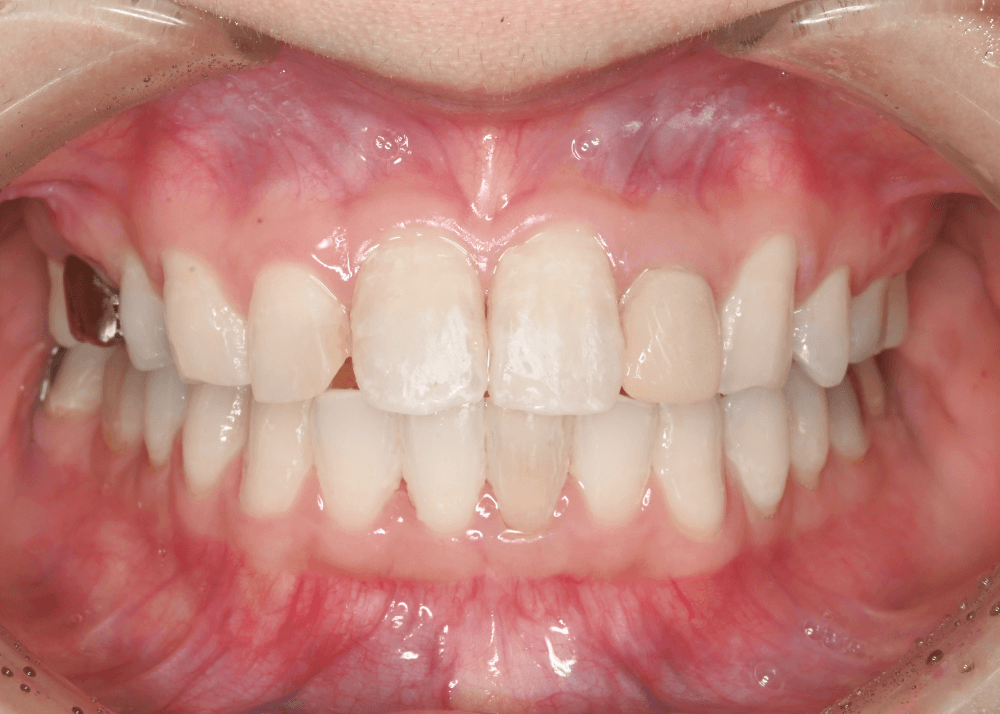

治療後の変化

治療後は、舌側に倒れていた前歯の傾きが改善しています。

前歯のポジションが適正化されたことで、スマイル時に奥まって見えていた歯の見え方が改善し、より自然な印象になっています。

また、唇を内側から支える「口唇サポート」が回復し、横顔の印象にも変化がみられました。

本症例では、噛み合わせを維持しながら上下歯列を前方へ移動させ、前歯の傾斜を整えることで、スマイル時の歯の見え方や立体感の改善を図りました。

治療前後の写真比較

治療前

治療後(32か月)